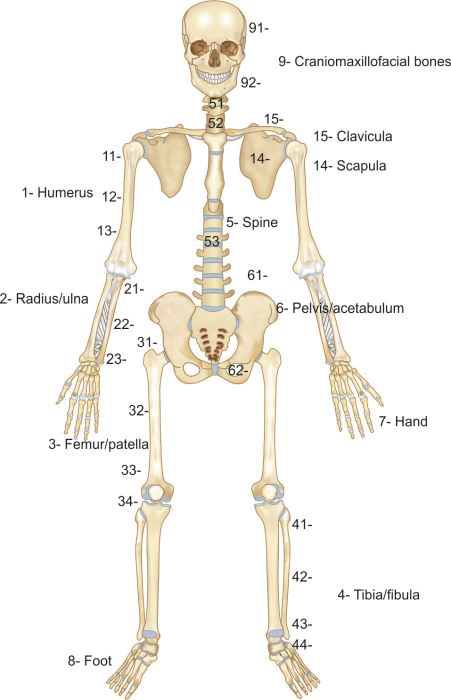

AO classification (Muller AO/OTA classification): This is a unique and comprehensive classification (Boxes 1.2 and 1.3) which can be applied to fracture of all bones. It is an alphanumerical classification, i.e. numbers and alphabets are used to classify a fracture. Recently a pediatric version has also been published.

In AO classification each major bone is given a number (Fig. 1.15) like humerus, forearm bones, femur and leg bones have been assigned 1, 2, 3 and 4 respectively. Each long bone is divided into three parts or segments; proximal segment, diaphysis and distal segment which are assigned 1, 2 and 3 number respectively. Each part is further divided into types (Table 1.4).

Types of proximal and distal segment fractures are classified as:

-

A—Extraarticular

-

B—Partial articular

-

C—Complete articular

Types of diaphyseal fractures are classified as:

-

A—Simple

-

B—Wedge

-

C—Complex

Each type is further divided into groups and subgroups which differ from bone to bone.